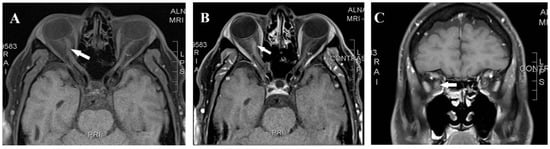

A 42-year-old man presented in February 2018 with right-eye pain and progressive visual loss over two weeks. The patient was in his usual state of health with no medical illness other than chronic migraines managed by topiramate. He has no family history of autoimmune disease or neurological disease but mentioned a case of blindness in a maternal uncle, which was attributed to glaucoma. Upon examination, visual acuity was reduced to hand motion OD and 20/20 OS, with a right relative afferent pupillary defect. Fundus examination showed optic disk hyperemia in the right eye; the left eye was normal. Visual evoked potential (VEP) showed an absent right-eye response, and the left-eye P100 = 112 ms. Automated Humphrey visual field testing showed a dense central scotoma in the right eye. Laboratory evaluation and a routine autoimmune panel, like antinuclear antibodies (ANAs), in addition to negative aquaporin-4 antibody (AQP4 Ab) and anti-myelin oligodendrocyte glycoprotein (MOG) antibodies, were negative. Cerebrospinal fluid (CSF) analysis was unremarkable, including negative oligoclonal bands. Brain and spinal MRI were normal, while orbital MRI revealed right-optic-nerve enhancement and mild enlargement (Figure 1). Moreover, metabolic, toxicological, and infectious serological studies were negative. He was treated with intravenous methylprednisolone followed by oral prednisone and plasma exchange with minimal recovery (the right eye improved from hand motion to counting fingers at a 50 cm distance). Azathioprine at a dose of 2 mg/Kg was started for the presumptive diagnosis of idiopathic autoimmune optic neuritis.

Figure 1. Magnetic resonance imaging axial T1 pre-contrast (A), axial T1 post-contrast (B), and coronal T1 post-contrast (C) showed right-optic-nerve mild enhancement and enlargement (arrow).